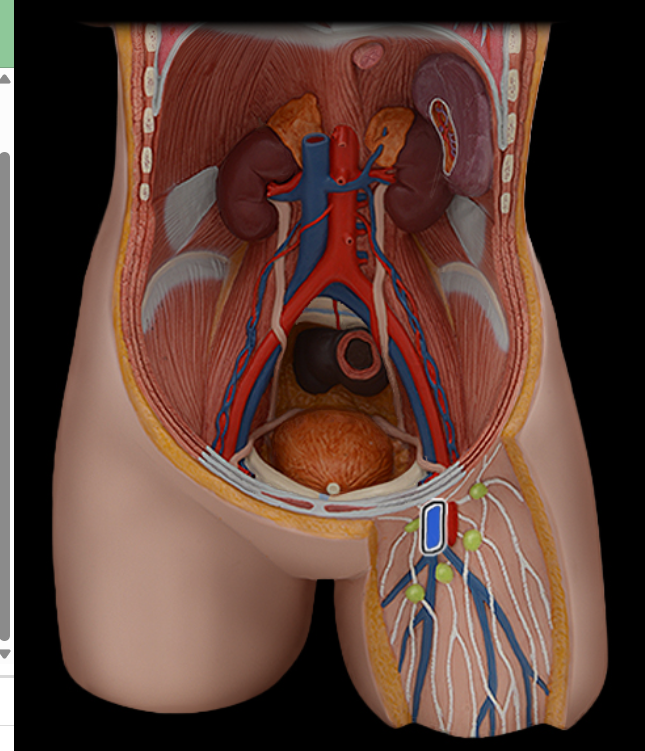

Abdominal aorta

Common iliac a.

Common iliac v.

External iliac a.

External iliac v.

Femoral a.

Femoral v.

Gonadal a.

Gonadal v.

Inferior vena cava

Lumbar a.

Lumbar v.

Renal a.

Renal v.

Superior mesenteric a.